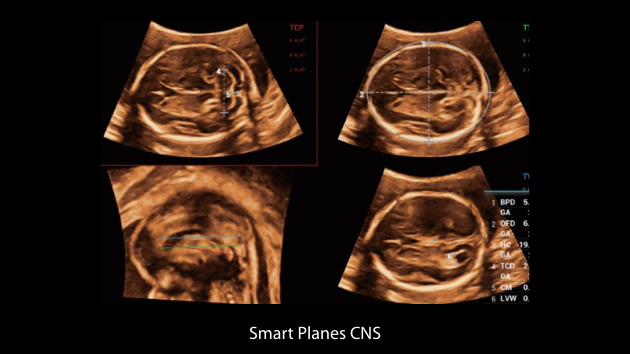

The Nuewa I9, dedicatedly designed for women and neonatal healthcare, providing an innovative experience from inside out.?These innovations are developed based on in-depth insights into complex clinical scenarios, providing accurate and timely answers as well as outstanding efficiency and remarkable user experience.

Clinical Images